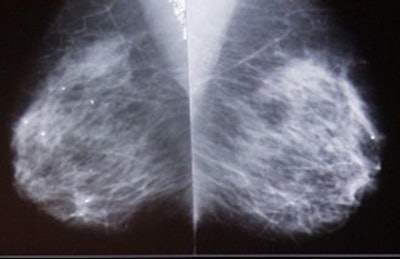

According to the results, the callback rate with DBT-P was 5.1%, 37% lower than the average conventional callback rate of 8% in a screening setting. The chart below details the DBT and CM reading outcomes paired with American College of Radiology (ACR) outcome scores.

| Courtesy of Richard Moore. |